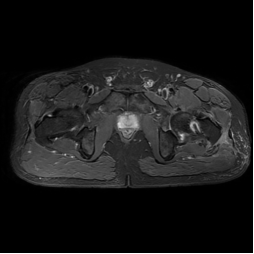

术前各学科各司其职、精心筹备,在徐永清教授带领指导下给予患者行“术中给予左侧股骨头病损切除、减压、带骨方肌骨瓣移植术”,历时1小时,手术取得成功,患者安返病房,术后给予卧床休养、辅助专科药物,患者左髋疼痛及髋关节功能恢复良好,术后第十天出院。

术后MRI